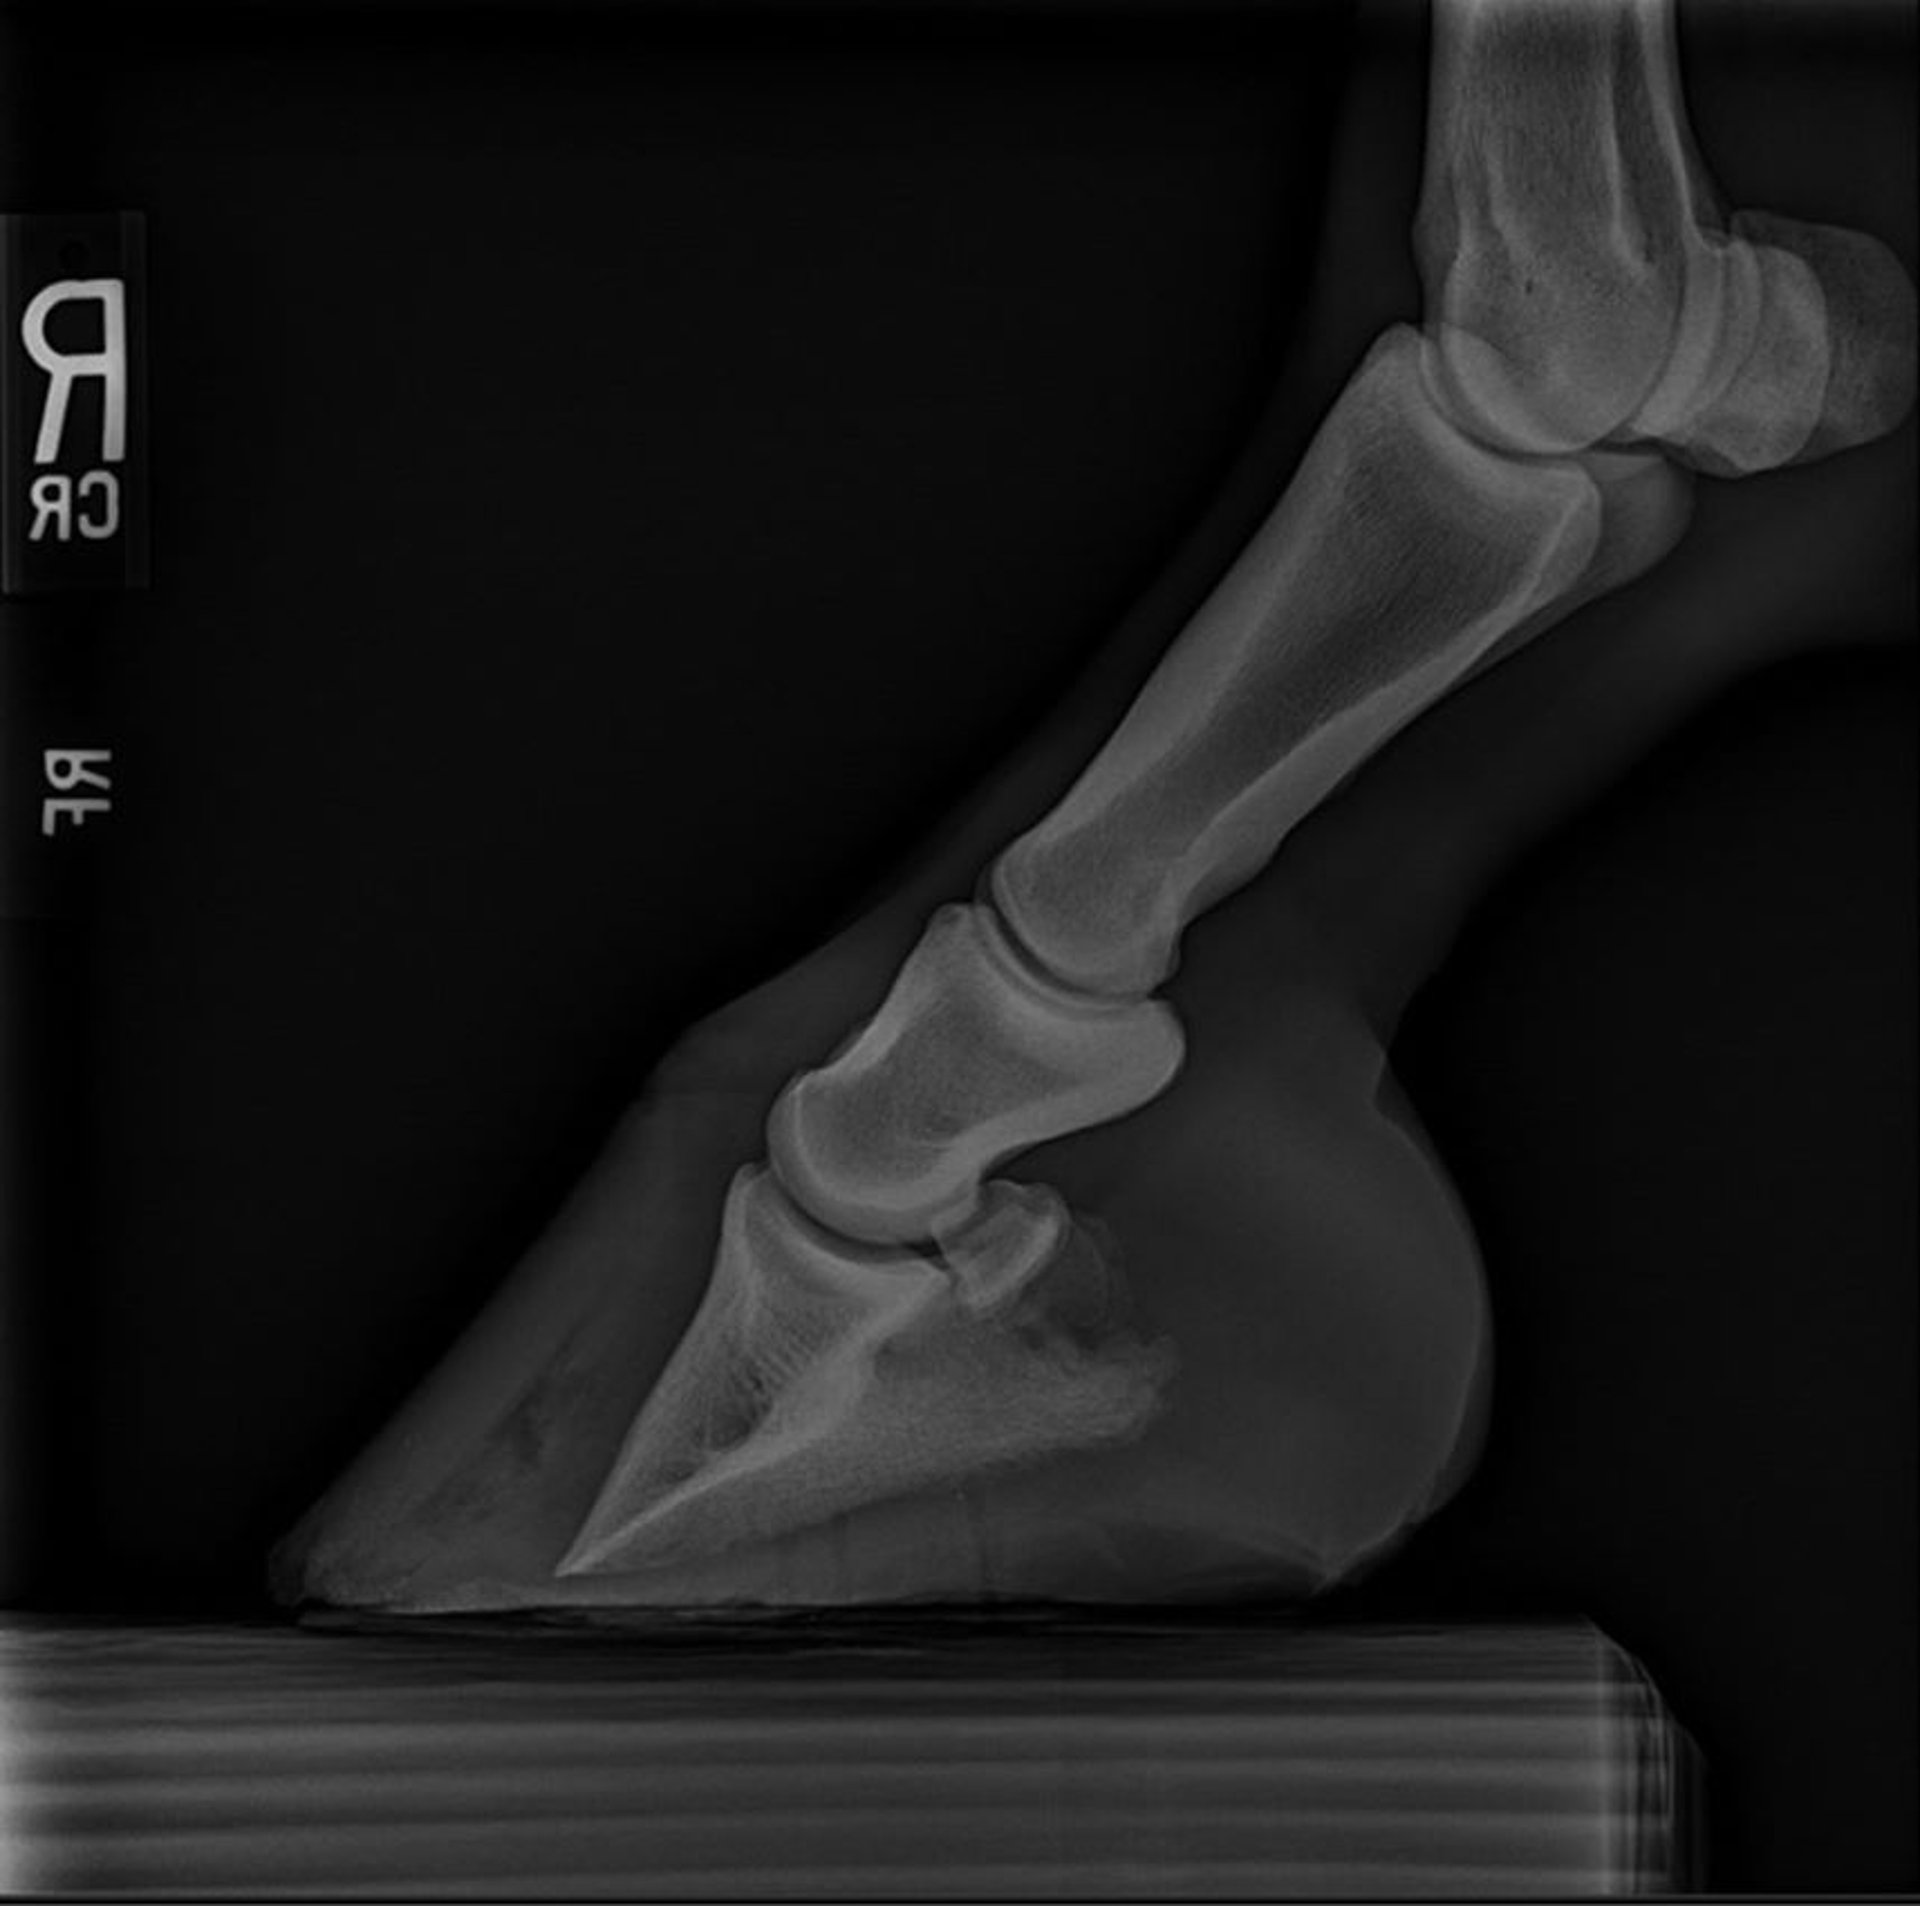

Radiografía lateromedial que muestra una laminitis rotacional grave en el casco de un caballo: la superficie dorsal de P3 ya no es paralela a la pared dorsal del casco. El rastreo de gas es evidente en la zona de separación de la pared del casco.

Cortesía del Dr. Brian Beasley.